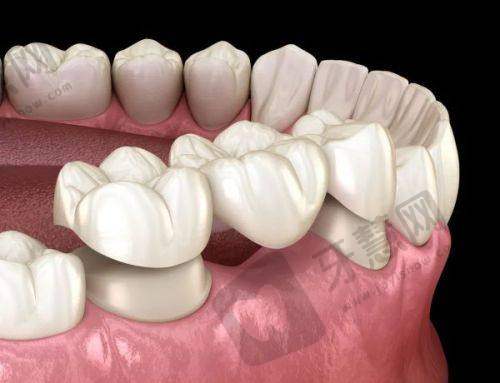

【特色项目】BPS全口吸附性义齿修复是核心亮点,具备不手术、无疼痛、无创伤、稳固性强、美观性高、性价比高等优点,能快速修复全口咀嚼功能;种植牙项目注重植体与牙槽骨的稳固性,减少邻牙受损与并发症风险。

【特色项目】口腔修复是核心优势,通过美学设计让修复后的牙齿与原生牙自然融合,提升笑容自信。

【特色项目】牙齿矫正结合数字化技术提升精细度,牙齿美白采用安心有效的方式,烤瓷牙修复注重美学与功能的结合。